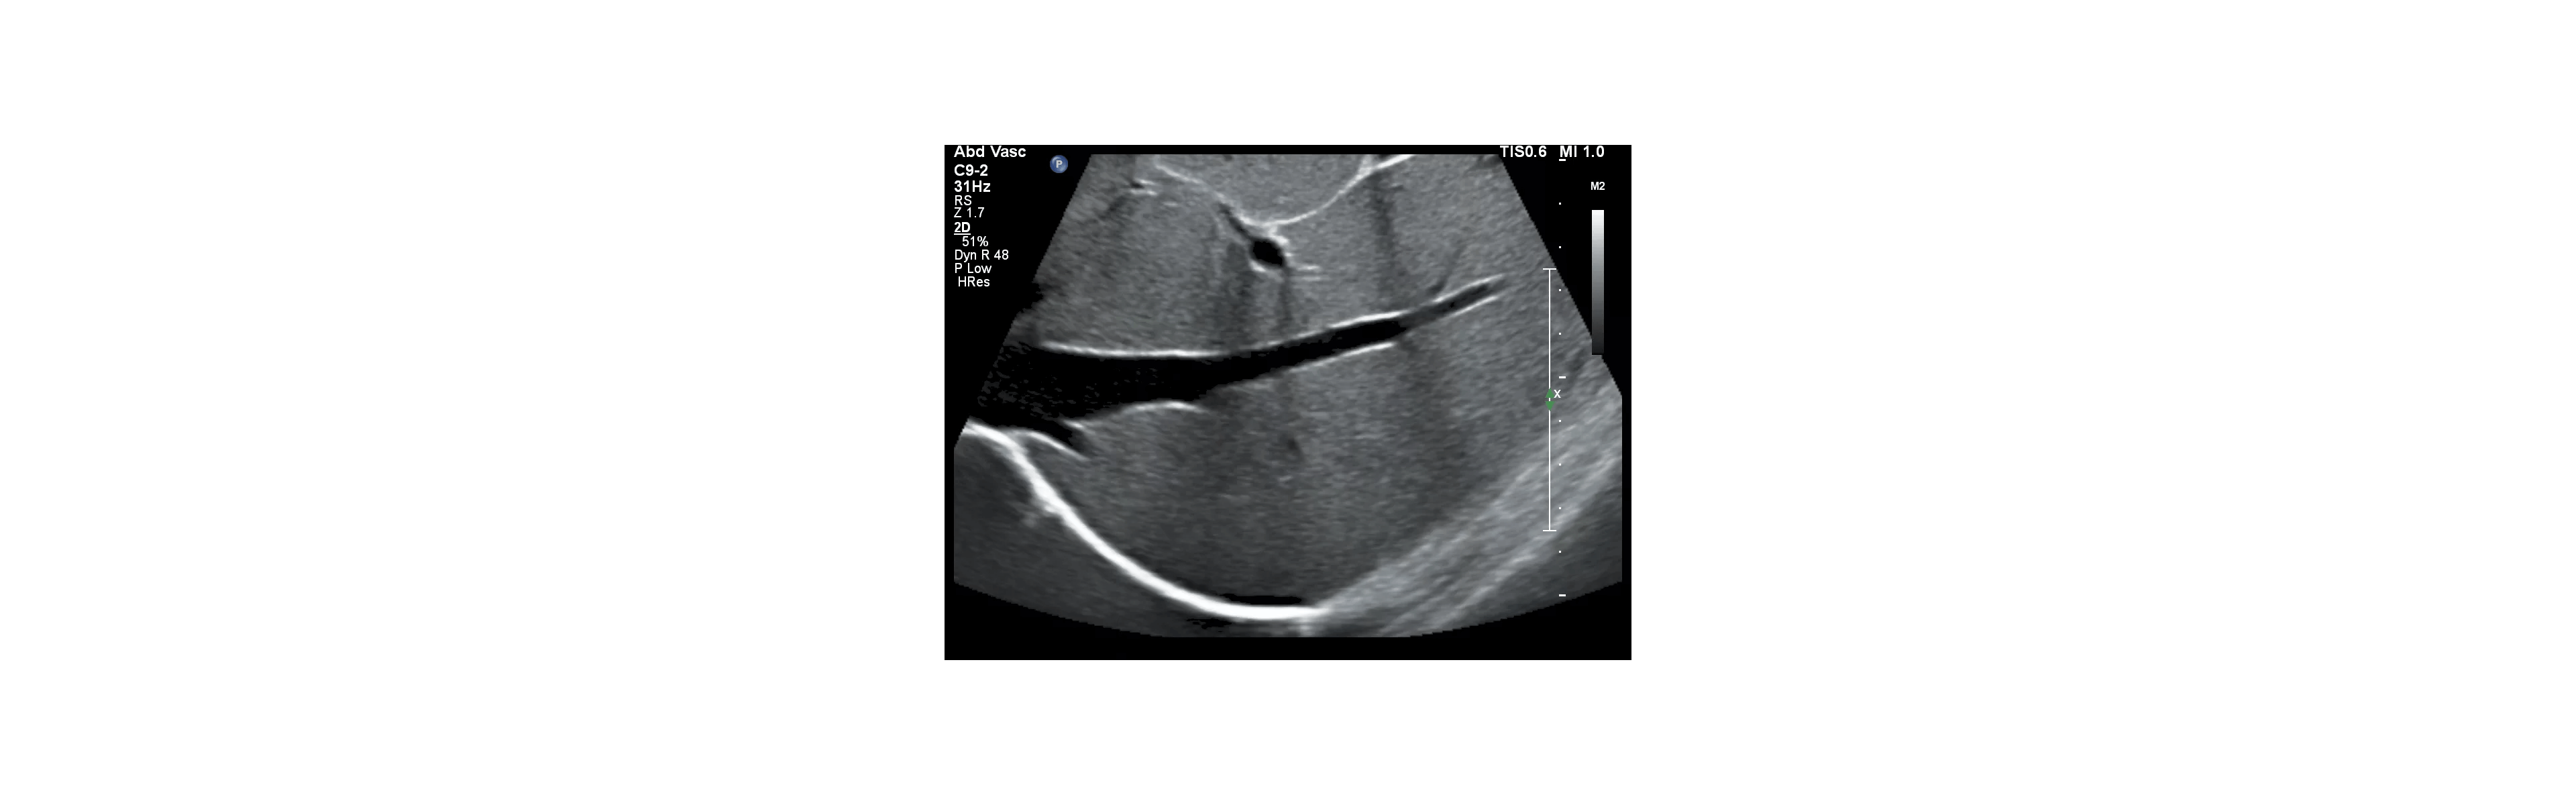

Vroegtijdige detectie van galstenen, nierstenen, cystes, myomen, of zwangerschap.

Beoordelen van buikklachten of pijn in de onderbuik zonder eerst naar een specialist te verwijzen.

• opsporen van vocht in de buik of longen

• beoordelen van spier- of peesproblemen